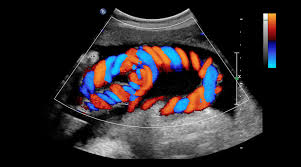

Color Doppler

Assesses blood flow in arteries and veins to detect blockages, clots, and vascular issues.

• Doppler Studies (Blood flow & vascular analysis)